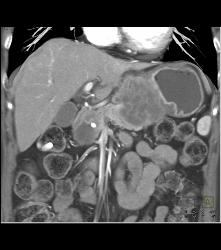

Antral Carcinoma With Adenopathy